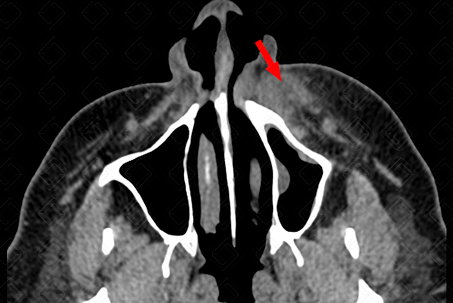

Descrição das figuras: Paciente com densificação dos planos adiposos na região maxilar esquerda, sem extensão orbitária, compatível com celulite de face (setas vermelhas).

• Tomografia computadorizada da face: Observa-se a densificação dos planos adiposos, podendo haver ainda a presença de coleções no estudo pós-contraste (figuras 1 e 2);